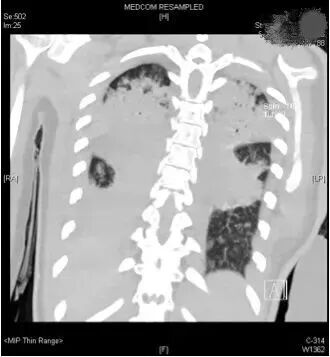

令人惊讶的是,这次复查提示两肺几乎全部实变!吸入100%的纯氧,小文的氧分压才勉强达标。如果病情再继续恶化下去,就需要上体外膜肺氧合机(ECMO)了。短短二三天时间,一个健康活泼的花季少女被摧残得奄奄一息。

影像检查示双肺几乎完全实变(医院供图 来源:新华社)